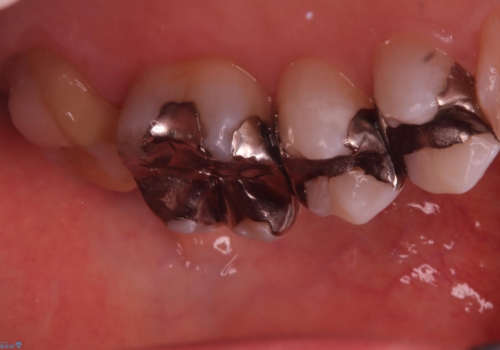

保険適用のメタルインレーと歯質の境目にう窩ができており、補綴物のやり替えとなりなした。

メタルインレーを除去したところう窩が深く、遠心の健歯質が歯肉縁下深くに位置したためディスタルウェッジ術を行い骨と歯肉の高さを下げた上で補綴しています。

元々インレーが入っていましたが、残存歯質量が少なく破折のリスクを説明しジルコニアクラウンでのやり替えとなりました。